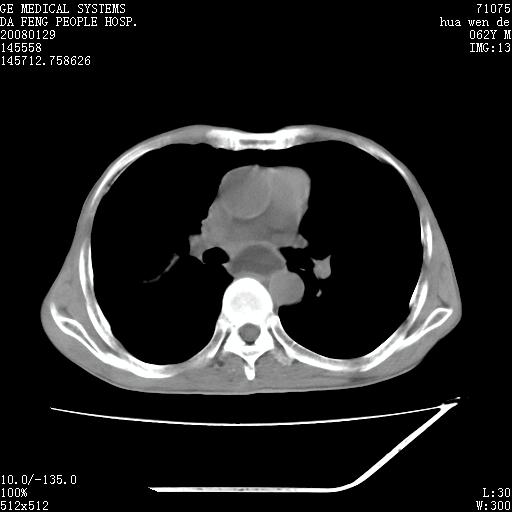

男性,67岁。作肺部检查时发现

理由:1、右上肺内病灶,空洞形成,有液平。

2、肺内多处炎症。

1.整个食管扩张,未见明显占位性病变,贲门区亦未见明显占位病变,考虑:贲门失驰缓症;

2.右上肺病变边缘可见毛刺,囊壁厚度不均匀,周围境界较清楚,未见炎性渗出性影,右上肺外带可见片状影,边缘不清,考虑:肺癌伴空洞形成、右上肺炎。

食管全程扩张,壁均匀不厚,喷门失弛缓症

右上肺空洞可见液平,临近肺野磨玻璃密度,考虑1.结核2.脓肿